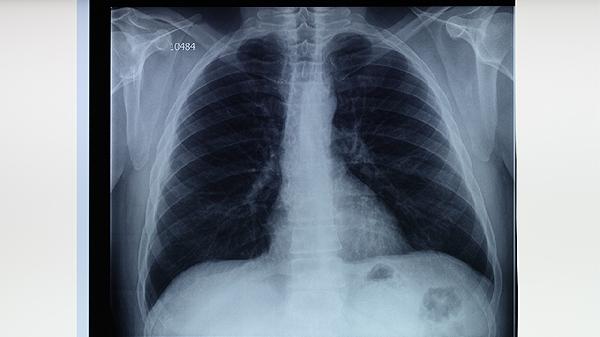

肺结核患者适合适量食用苹果、梨、香蕉、猕猴桃、橙子等水果,有助于补充营养并促进康复。肺结核是由结核分枝杆菌引起的慢性传染病,患者需在医生指导下规范用药,同时通过饮食调理增强免疫力。